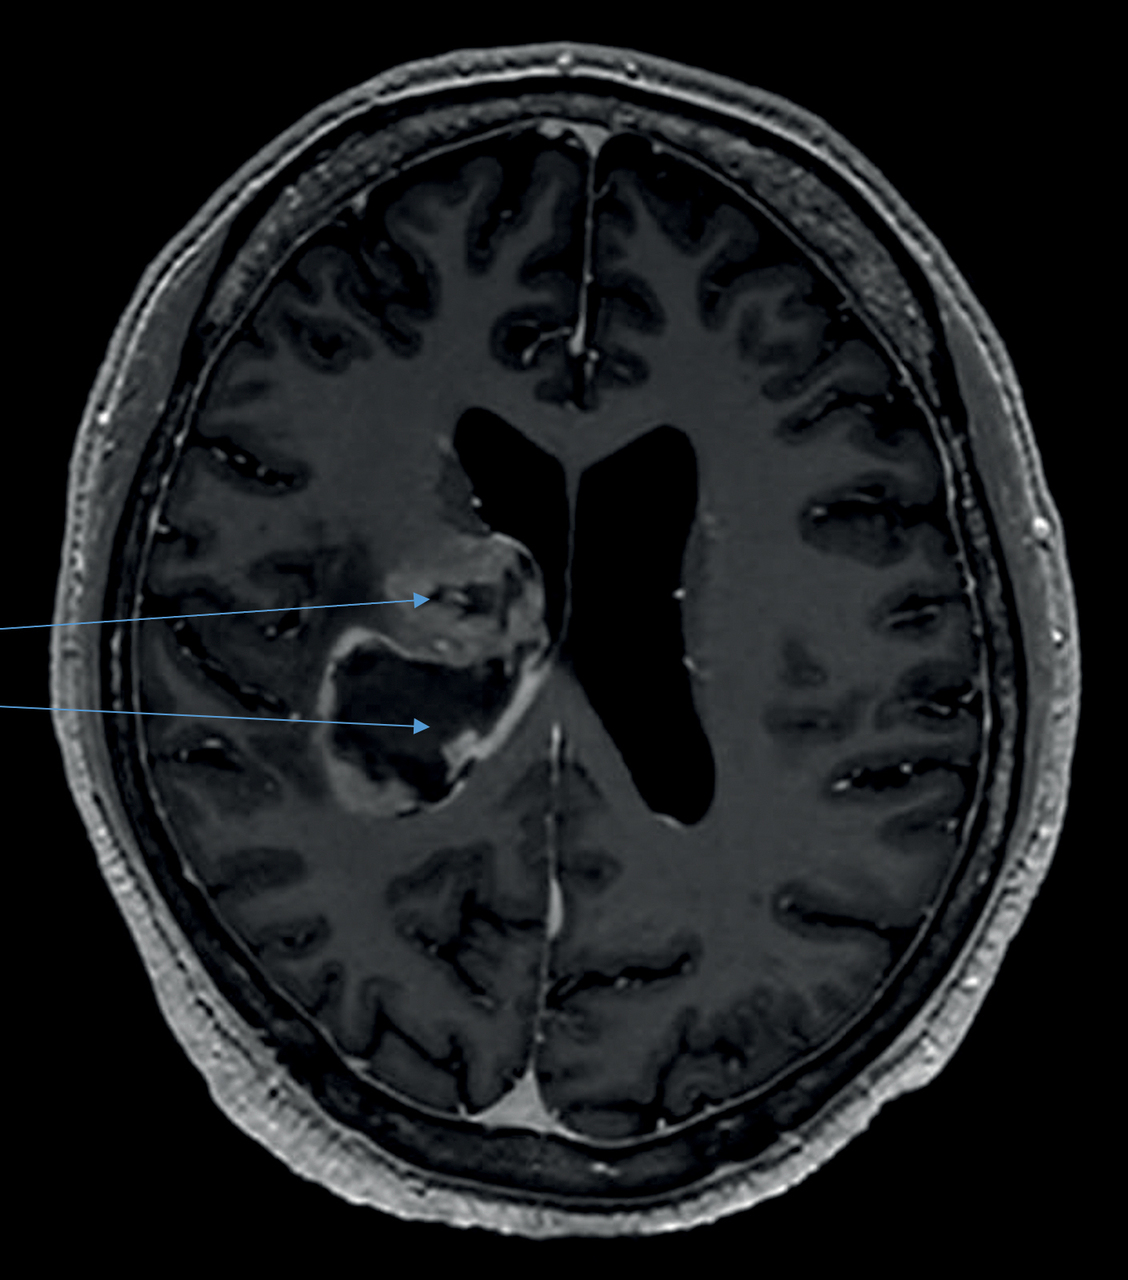

L’IRM montre une lésion rehaussée, à paroi épaisse, charnue et nécrotique capsulolenticulaire et thalamique postérieure droite, étendue à la paroi ventriculaire et à la substance blanche profonde de la région centrale. Il existe un effet de masse modéré avec déplacement du troisième ventricule et élargissement du ventricule controlatéral. La biopsie cérébrale confirme le diagnostic de glioblastome.